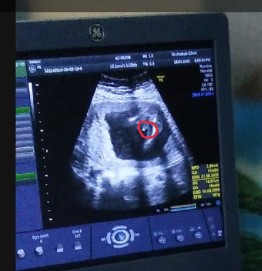

ขอดูใบซาวเด็ก ผช. ของแม่ๆ หน่อยค่ะ ?

ในภาพเป็น ผช ใช่ไหมค่ะ พอดีหมอขอชัวร์ๆ เดือนหน้า เลยสอบถามแม่ๆ ที่มีประสบการณ์ลูกชาย หน่อยค่ะ ?ขอดูใบอัตตลาซาวเด็ก ผช . หน่อยจร้าาา? ถาพไม่ชัดเพราะถ่าย VDO มาจร้า ??

ผช คะ

BOY